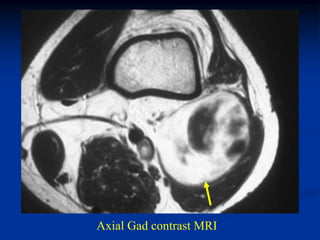

Case #1199

30 year male with

myxoid liposarcoma

posterior thigh

Sagittal T-1 MRI

Sagittal T-2 MRI

tumor

Axial T-1 MRI

Axial Gad contrast MRI

Coronal Gad

contrast MRI

Case #1199 30 yearmale with myxoid liposarcoma posterior thigh Sagittal T-1 MRI